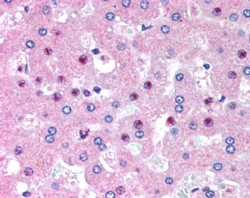

- Main image

- Experimental details

- STJ71088 (2. 5µg/ml) staining of paraffin embedded Human Liver. Steamed antigen retrieval with citrate buffer pH 6, AP-staining.